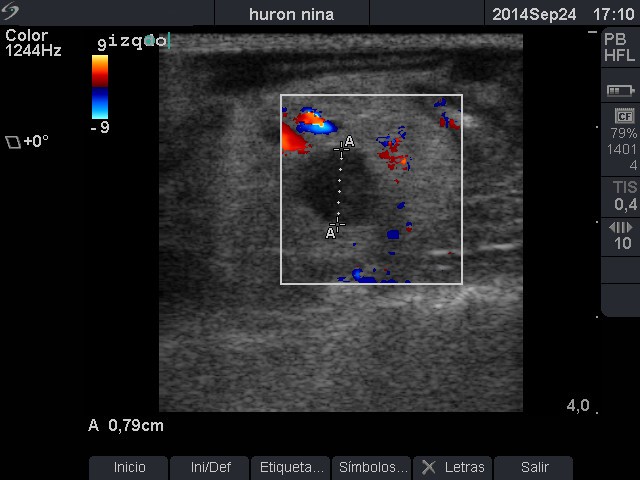

Glándula adrenal izquierda globosa con aumento de tamaño (0,79cm).

Hiperplasia adrenal izquierda.